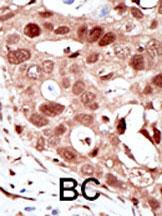

| WB, IHC-P, E |

| Dilution | WB~~1:1000 IHC-P~~1:50~100 E~~Use at an assay dependent concentration. |